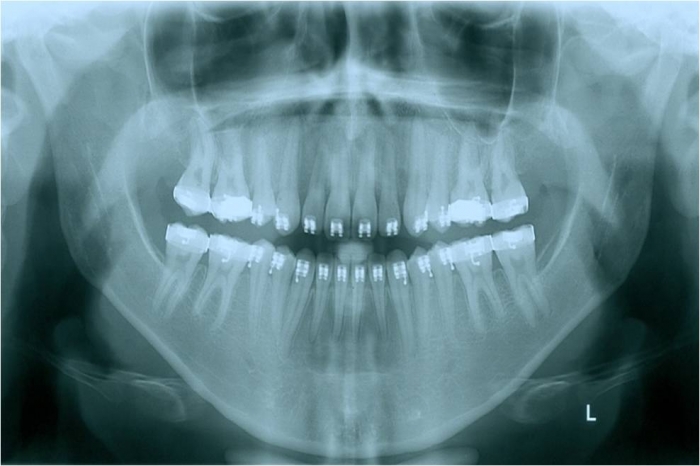

Raio x inicial